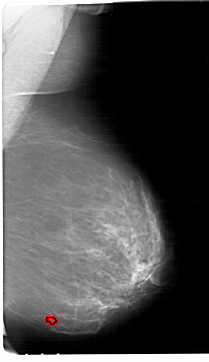

ics_version 1.0 filename A-1265-1 DATE_OF_STUDY 25 1 1995 PATIENT_AGE 48 FILM FILM_TYPE REGULAR DENSITY 3 DATE_DIGITIZED 23 7 1998 DIGITIZER HOWTEK 43.5 SEQUENCE LEFT_CC LINES 6556 PIXELS_PER_LINE 4111 BITS_PER_PIXEL 12 RESOLUTION 43.5 NON_OVERLAY LEFT_MLO LINES 6616 PIXELS_PER_LINE 4081 BITS_PER_PIXEL 12 RESOLUTION 43.5 NON_OVERLAY RIGHT_CC LINES 6646 PIXELS_PER_LINE 4066 BITS_PER_PIXEL 12 RESOLUTION 43.5 OVERLAY RIGHT_MLO LINES 6871 PIXELS_PER_LINE 3961 BITS_PER_PIXEL 12 RESOLUTION 43.5 OVERLAY |

FILE: A_1265_1.RIGHT_MLO.OVERLAY TOTAL_ABNORMALITIES 1 ABNORMALITY 1 LESION_TYPE CALCIFICATION TYPE PLEOMORPHIC DISTRIBUTION CLUSTERED LESION_TYPE MASS SHAPE IRREGULAR MARGINS ILL_DEFINED ASSESSMENT 4 SUBTLETY 3 PATHOLOGY BENIGN TOTAL_OUTLINES 1 BOUNDARY |